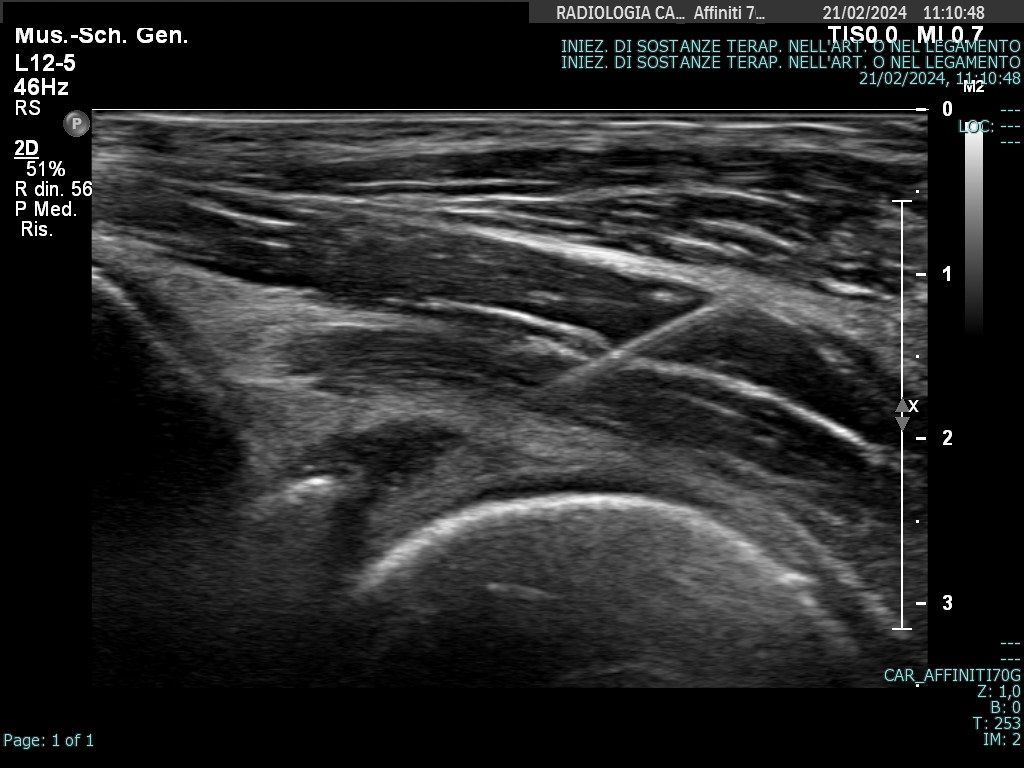

La Dottoressa Morgano Maria Chiara si è laureata in Medicina e Chirurgia presso l’università degli studi di Palermo con 110/110 e Lode. Ha conseguito la specializzazione in Radiologia col massimo dei voti e Lode presso l’università degli studi dell'Insubria. Durante il percorso di specializzazione presso l'Ospedale di Varese "Ospedale di Circolo e Fondazione Macchi", ha acquisito buone competenze diagnostiche come radiologo generale sull'utilizzo di varie metodiche di imaging (RX, ecografia, Tomografia Computerizzata, RM), ma ha dedicato gran parte della sua formazione alla Radiologia Muscolo-scheletrica Diagnostica ed Interventistica, maturando esperienze e competenze nel trattamento ecoguidato di patologie muscolo-tendinee. Ha completato il suo percorso di specializzazione presso "Columbus Clinic Center" a Milano, dove ha avuto la possibilità di seguire un vasto numero di Risonanze su atleti e sportivi come ad esempio giocatori di A.C. Milan, acquisendo competenze specialistiche nell’ambito delle patologie sportive. Ha lavorato come libera professionista presso Vari studi privati nella città di Siena ove praticava l'ossigeno-ozonoterapia sulla colonna per poi lavorare come dirigente medico presso l'Azienda Ospedaliera di Busto Arsizio. Ha lavorato presso l'Ospedale di Carate Brianza, dove ha avviato l'ambulatorio di ecografie muscolo-tendinee ed infiltrazioni eco-guidate. Da gennaio 2026 lavora presso l’ospedale IRCCS Multimedica di Sesto S. Giovanni dove esegue ecografie ed infiltrazioni ecoguidate. Svolge inoltre attività libero-professionale in ambito di Medicina Estetica, integrando alla visita clinica una valutazione ecografica accurata del volto. Questo le permette di utilizzare le competenze ecografiche maturate nella radiologia anche nei trattamenti estetici, al fine di ridurre il rischio di complicanze, indirizzare con precisione l’area da trattare e gestire in modo più efficace eventuali complicanze.

Foto e video